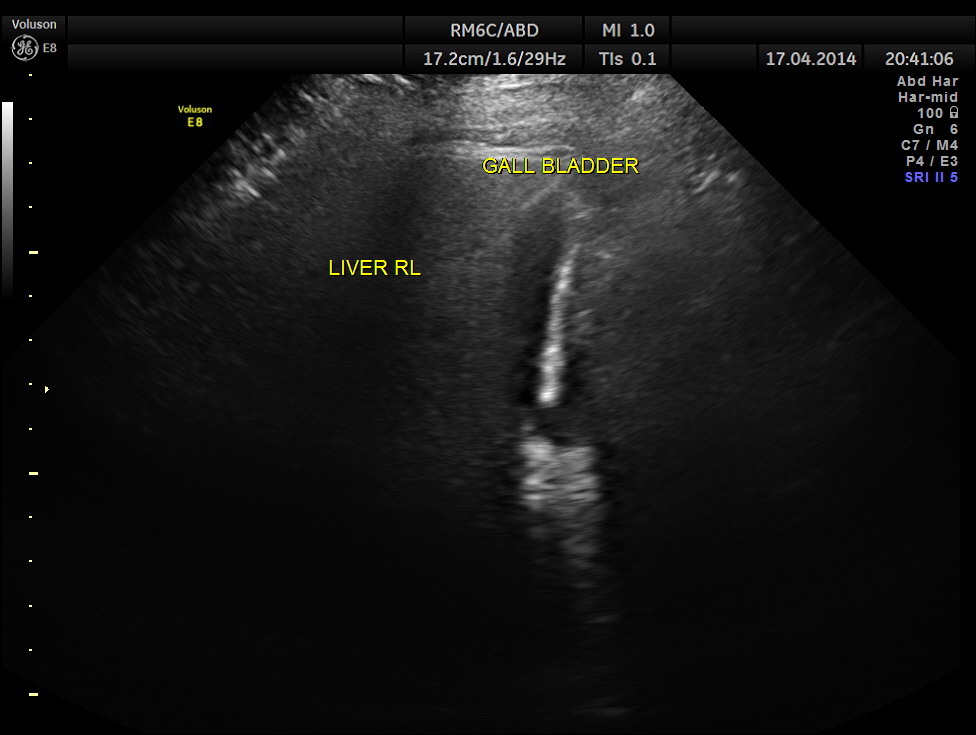

This was a 48 year old lady who was seeing me on and off for diabetes mellitus and systemic hypertension . She came to me a few months ago for uncontrolled diabetes. Her Blood sugar was around 400 mgms/dl and she was started on insulin for better control. The patient had history of irregular periods with history of menorrhagia for the last 3 cycles .She again came 2 weeks later for complaints of fever on and off. Her blood sugar had come under control . On clinical examination a mass was felt in the right hypochondrium and she went through an abdominal scan.

Two distinct mass lesions were seen in the right side of the abdomen in the lumbar and hypochondriac regions . Though they appeared distinct from the liver , it was a bit confusing.

The mass lesions are seen below.